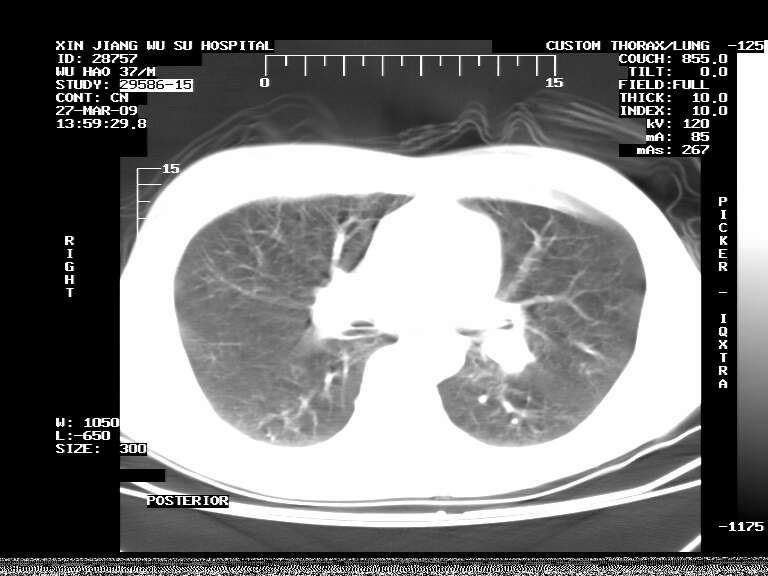

男,37岁,体检胸透发现阴影。

患者体检发现 无症状 左肺下叶占位,边缘模糊,可见血管聚束、分叶、胸膜牵拉,增强呈不均匀性强化。 首先考虑左肺下叶周围型肺癌,建议穿刺活检。

左肺下叶见一结节病变,边缘欠清不光滑,与胸膜粘连且胸膜局限性增厚,注药后呈环形强化,动脉期壁呈明显点环状强化,静脉期壁强化减低,中心密度低无强化,灶周无明显的卫星灶和水肿区(晕征)---考虑周围性肺癌,不除外感染性病变,建议穿刺活检。

左肺下叶软组织病灶,密度较高,内见点状钙化,其周围见子灶,邻近胸膜扁平样增厚.c+病灶强化明显,中心强化弱.诊断:左肺下叶结核瘤.

左肺下叶大片实变影,内靠胸膜见不规则更高密度结节灶,边缘强化,相邻胸膜增厚,胸膜下脂肪线存在。考虑炎症,结核可能。